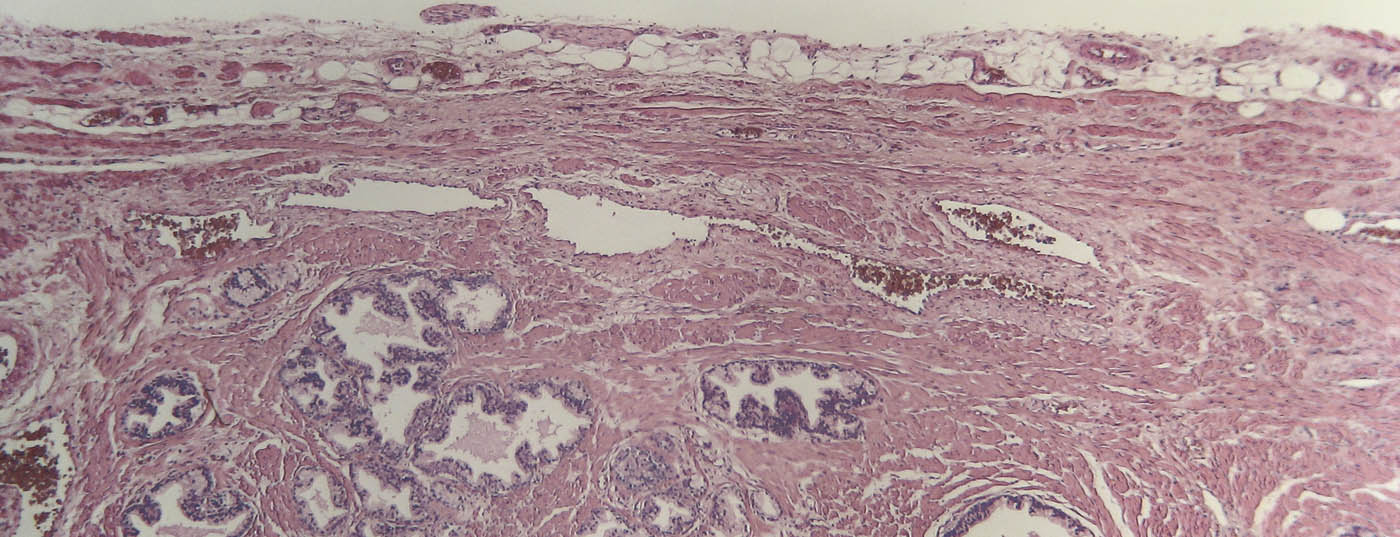

prostata_histo

• Kastrationsrefraktäres Prostatakarzinom (CRPC)

Welche neuen Therapieoptionen gibt es?

Die deutliche Zunahme der zur Verfügung stehenden therapeutischen Mittel beim CRPC ist erfreulich. Im Zentrum einer jeden Therapie sollte der Erhalt der Lebensqualität mit einer Reduktion von tumorspezifischen Komplikationen stehen. Aufgrund der Komplexität bei gleichzeitig fehlenden Vergleichsdaten empfehlen die aktuellen EAU-Guidelines bei mCRPC-Patienten generell ein multidisziplinäres Vorgehen und damit die Vorstellung in einem ­Tumorboard.